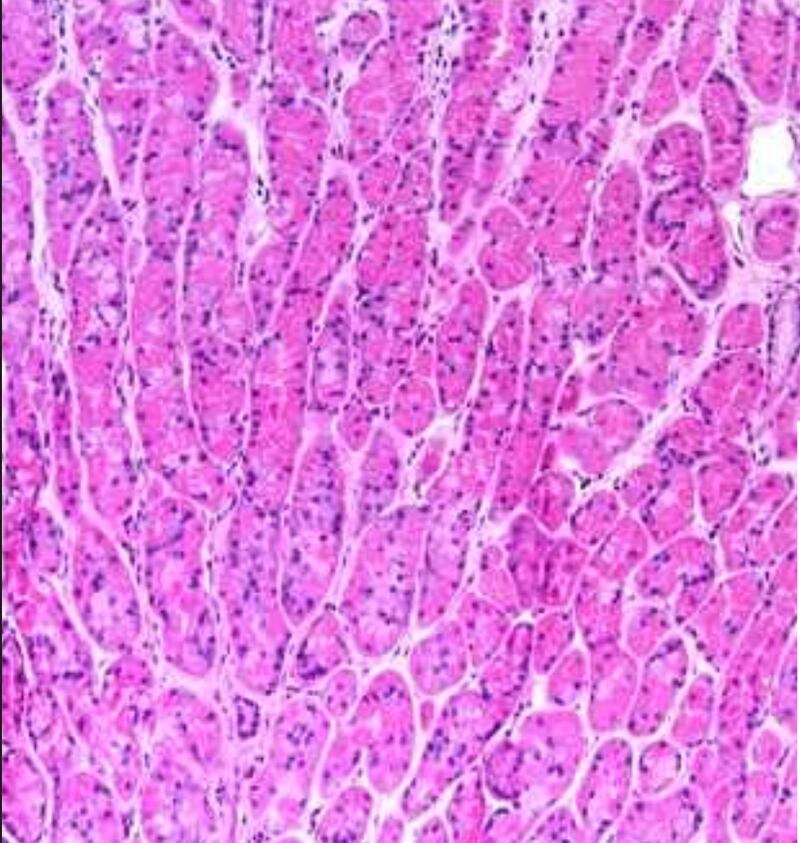

They went back to the basics, referring to old medical textbooks. They pored over microscope slides of the actual bile duct, peering at the stained images and trying to figure out what these alien tunnels could be. They tried a different stain, a trichrome one that colors collagen cobalt. These stains turned up normal, but modern medical textbooks offered no advice as to what those odd bright bands were.

This thing they were looking at, struggling to understand with its bizarre structure and rule-breaking form, was the interstitium, a space vaguely described in textbooks as where “extracellular fluid” is found, the fluid that isn’t contained within cells. What doctors had defined as “dense connective tissue” wasn’t dense connective tissue at all. In fact, they were all fluid-filled structures that only appeared to be densely compacted when tissues were made into slides, the fluid draining away, the collagen lattice collapsing onto itself.

“We always thought those cracks were, ‘Oh, we tore the tissue a little,’” Theise said as he flipped through slides that consistently showed the wavy, almost dancing, spaces that were in each slide. “But no, those tiny ‘cracks’ are the remnants of the interstitial spaces. For 200 years, we said these cracks were just tear artifacts.”